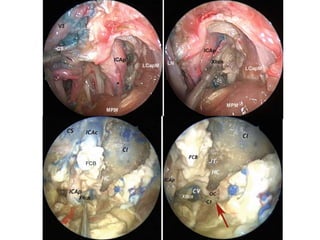

Gulfar segment of 6th nerve (GS in left picture ) ( gVIcn in right picture ) - The

gulfar segment can be identified at the intersection of the sellar floor and the

proximal parasellar internal carotid artery (ICA) (Barges-Coll et al. 2010 ).

ICAc cavernous portion of the internal carotid artery, IPS inferior petrosal sinus, PAp petrous apex, SPCG sphenopetroclival gulf, cVIcn cisternal segment of the

abducens nerve, gVIcn gulfar segment of the abducens nerve, pVIcn petrosal segment of the abducens nerve, white asterisks dura of the posterior cranial fossa –

The gulfar segment can be identified at the intersection of the sellar floor and the proximal parasellar internal carotid artery (ICA) (Barges-Coll et

al. 2010 ).

1. 6th N. crossing carotid at Petro-clival junction when viewing in lateral skull base

2. The gulfar segment can be identified at the intersection of the sellar floor and the

AICA anterior-inferior cerebellar artery, Cl clivus, CS cavernous sinus, ICAc cavernous portion

of the internal carotid artery, IPS inferior petrosal sinus, LPMVN lateropontomesencephalic

venous network, PBs pontine branches, PG pituitary gland, TPV transverse pontine vein, VA

vertebral artery, VN vidian nerve (bordered in yellow ), Vcn trigeminal nerve, VIcn abducens

nerve, yellow arrow cavernous portion of the abducens nerve